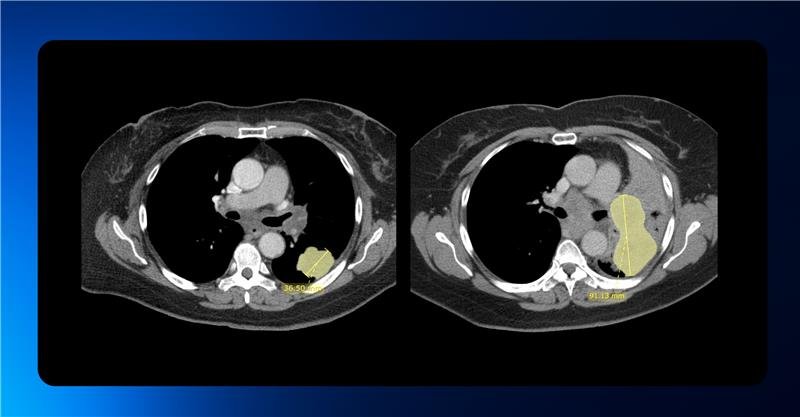

Streamlining RECIST Evaluation with AI

Designed to optimize radiology workflows, Quibim’s solution—integrated within the QP-Insights platform—leverages advanced deep learning algorithms to accelerate tumor response evaluation based on RECIST 1.1 criteria.

AI-driven tools are seamlessly embedded into the workflow to automatically detect, segment, measure, and track lesions in the lungs and liver. The algorithm is capable of identifying new lesions and monitoring existing ones across follow-up timepoints following the baseline scan.

Radiologists retain full control over the evaluation process, with the ability to manually adjust the AI-generated measurements and add lesions from other anatomical regions in an intuitive and user-friendly interface.

All data is automatically stored in a standardized digital format within the platform, enabling automated RECIST 1.1 response calculations and generating a final summary report of the complete assessment.